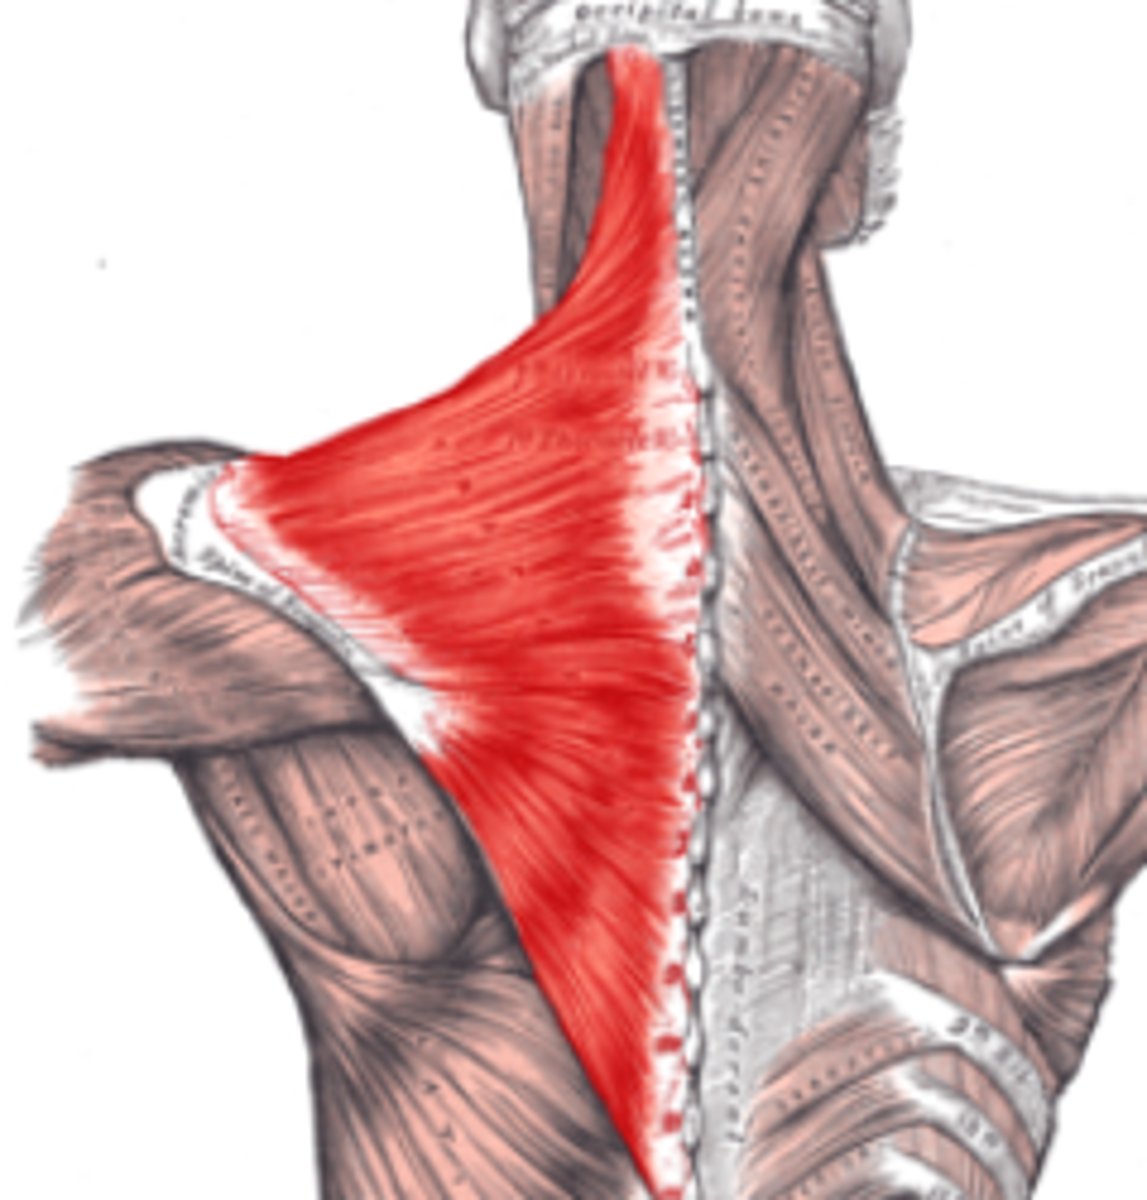

(Posterior axioappendicular and scapulohumeral muscles:) Superficial posterior axioappendicular muscles (extrinsic shoulder)

Trapezius and Latissimus dorsi

(Superficial posterior axioappendicular muscles (extrinsic shoulder):) Trapezius

-Elevates, depresses, and retracts scapula

-Accessory nerve (CN XI)